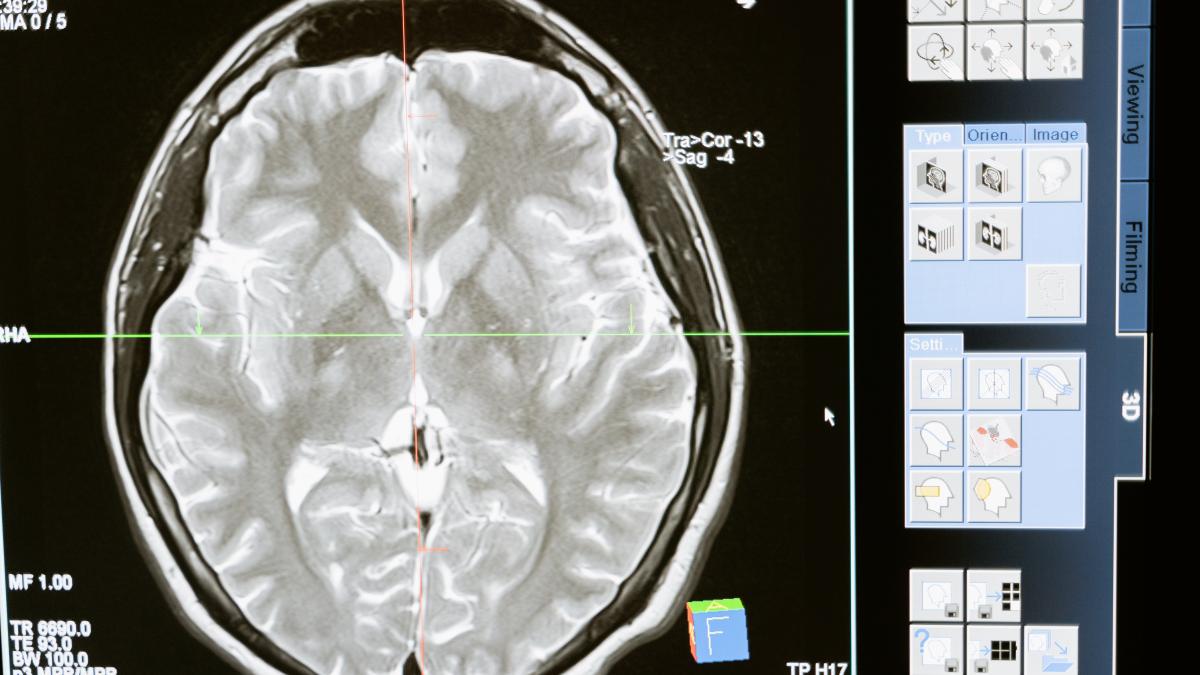

Poluarea ne afectează sănătatea mintală. Incendiile de vegetație și pesticidele cresc numărul cazurilor de demență în rândul populației

Incendiile de vegetație și folosirea pesticidelor în agricultură cresc riscul de demență pe tot parcursul vieții mai mult decât poluarea aerului din alte surse, potrivit unui nou studiu.

Un nou studiu de la Universitatea din Michigan, publicat în revista de specialitate JAMA, a constatat că dintre toate tipurile de poluare a aerului, incendiile de pădure și stropirea agricolă cu pesticide sunt cele mai dăunătoare când vine vorba de sănătatea creierului.

Autorii studiului au descoperit că particulele minuscule transportate în sus de aceste două surse – pe care le putem respira – sunt cel mai puternic asociate cu debutul demenței.